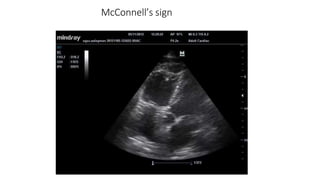

Echocardiogram

• Presence of unexplained right ventricular volume or pressure

overload should suggest the possibility of embolism and lead to

confirmatory testing.

• Trans Esophageal Echocardiography has better sensitivity and

specificity especially in cases of proximal embolus, reaching up to

90%. Compared to 50% in transthoracic echo.

• McConnell’s sign :

McConnell’s sign